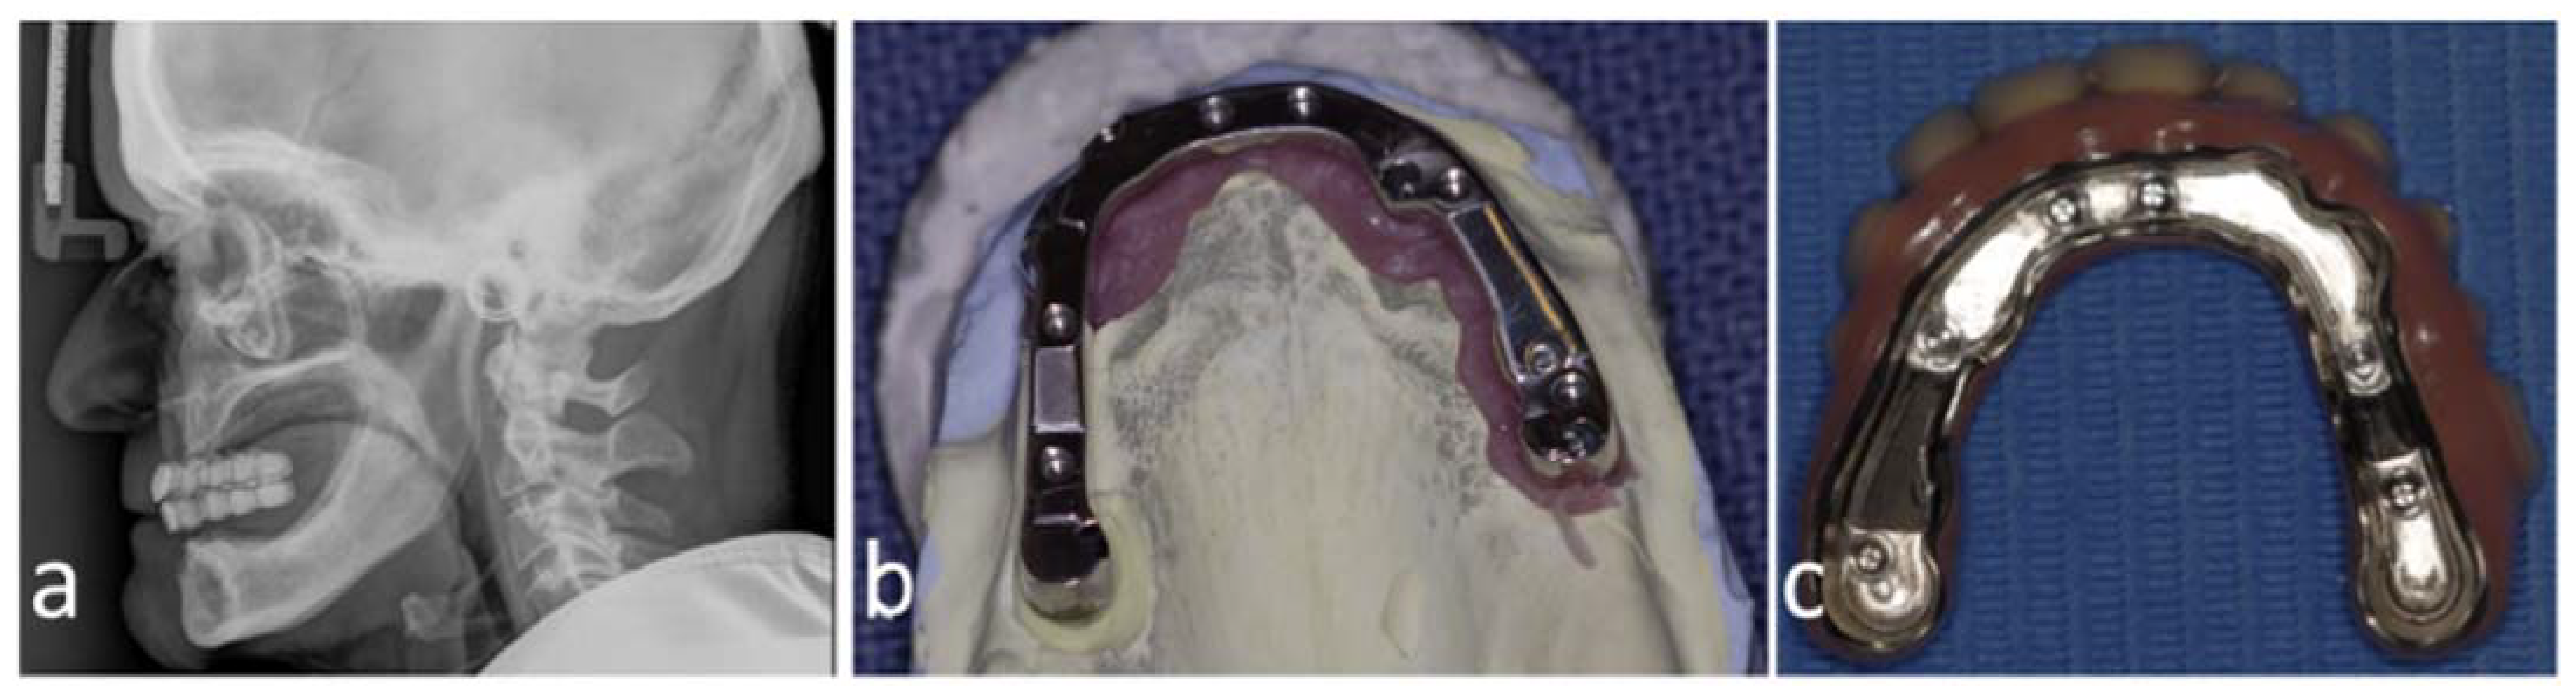

Figure 1.

Preoperative cephalogram of patient no. 2 with barium-sulfate-dyed mockup prosthesis demonstrating the desired tooth positioning (a), manufactured maxillary bar by Createch (b), and a secondary suprastructure (c).